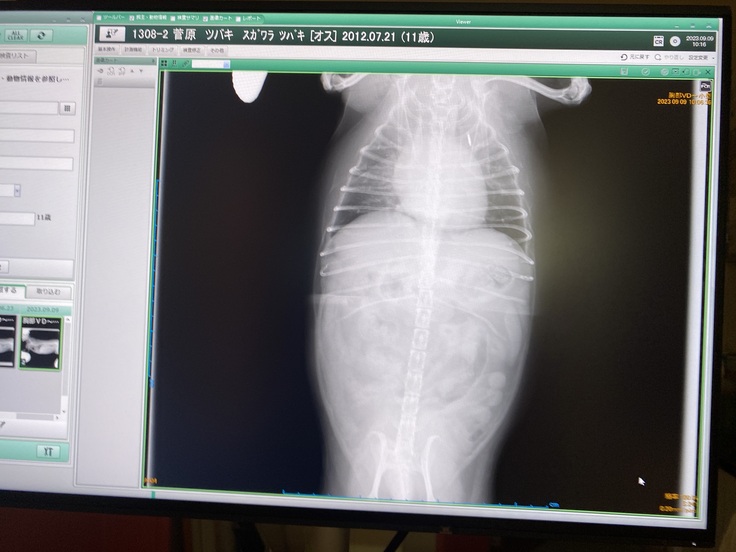

取り急ぎInstagramでご報告させていただいておりましたが、昨夜から舌をペチャペチャとする行動や細かい回数の多い咳が多かった為、今朝病院に連れていき、レントゲンと血液検査をしてきました。

結果は肺ではなく今度は胸水が溜まり始めていると言われました。

溜まっている場所は肺の中ではなく外側に位置する場所?らしいです。

肺水腫の場合は肺の中がスポンジが水を吸収していくように溜まっていくと先生は表現しておりました。

胸水が溜まると肺の外側からも水が溜まり、それが大きくなると更に肺を圧迫してしまい、息が苦しくなってしまったり、食欲が低下してしまうようです。

今は肺炎を引き起こしている状況のようです。